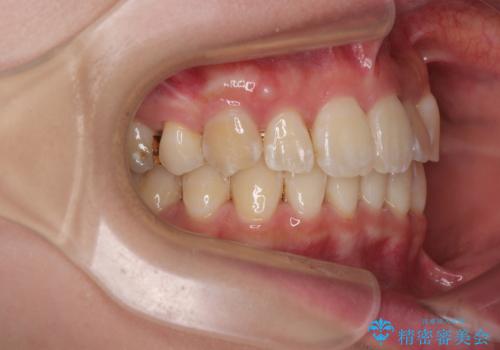

- 前歯1本が後ろ側に隠れてしまうほどのデコボコを気にして来院された患者様です。

前歯のデコボコが顕著なのはもちろんですが、左右ともに奥歯の咬み合わせに問題があり、上顎臼歯が前方位にある状態でした。

上顎は左右の第一小臼歯2本を、下顎は左右第二小臼歯2本を抜歯することで、奥歯の咬み合わせを改善しながら、デコボコを解消していくこととしました。

奥歯の咬み合わせ改善にはどうしても長期間を要します。

3年強とお伝えしておりましたが、予想通り3年3ヶ月で治療を終えることができました。